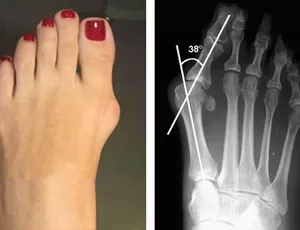

JOANETE

Um joanete, também conhecido como hálux valgo, é uma deformidade óssea que ocorre na articulação na base do dedão do pé. Essa condição é caracterizada por uma protuberância óssea que se forma na borda interna do pé, onde o dedão se encontra com o restante do pé.

Os sintomas de um joanete podem incluir dor, inchaço, vermelhidão e rigidez na articulação do dedão do pé. Esses sintomas podem piorar ao caminhar ou usar sapatos apertados. Em estágios mais avançados, o dedão do pé pode se desviar em direção aos outros dedos, causando deformidade adicional e dificultando a mobilidade.

Em casos mais graves, quando os sintomas são persistentes e impactam significativamente a qualidade de vida do paciente, ou quando a deformidade interfere na função do pé, a cirurgia pode ser considerada. Existem várias técnicas cirúrgicas disponíveis para corrigir um joanete, incluindo a remoção do tecido ósseo excessivo, realinhamento da articulação e correção da deformidade.